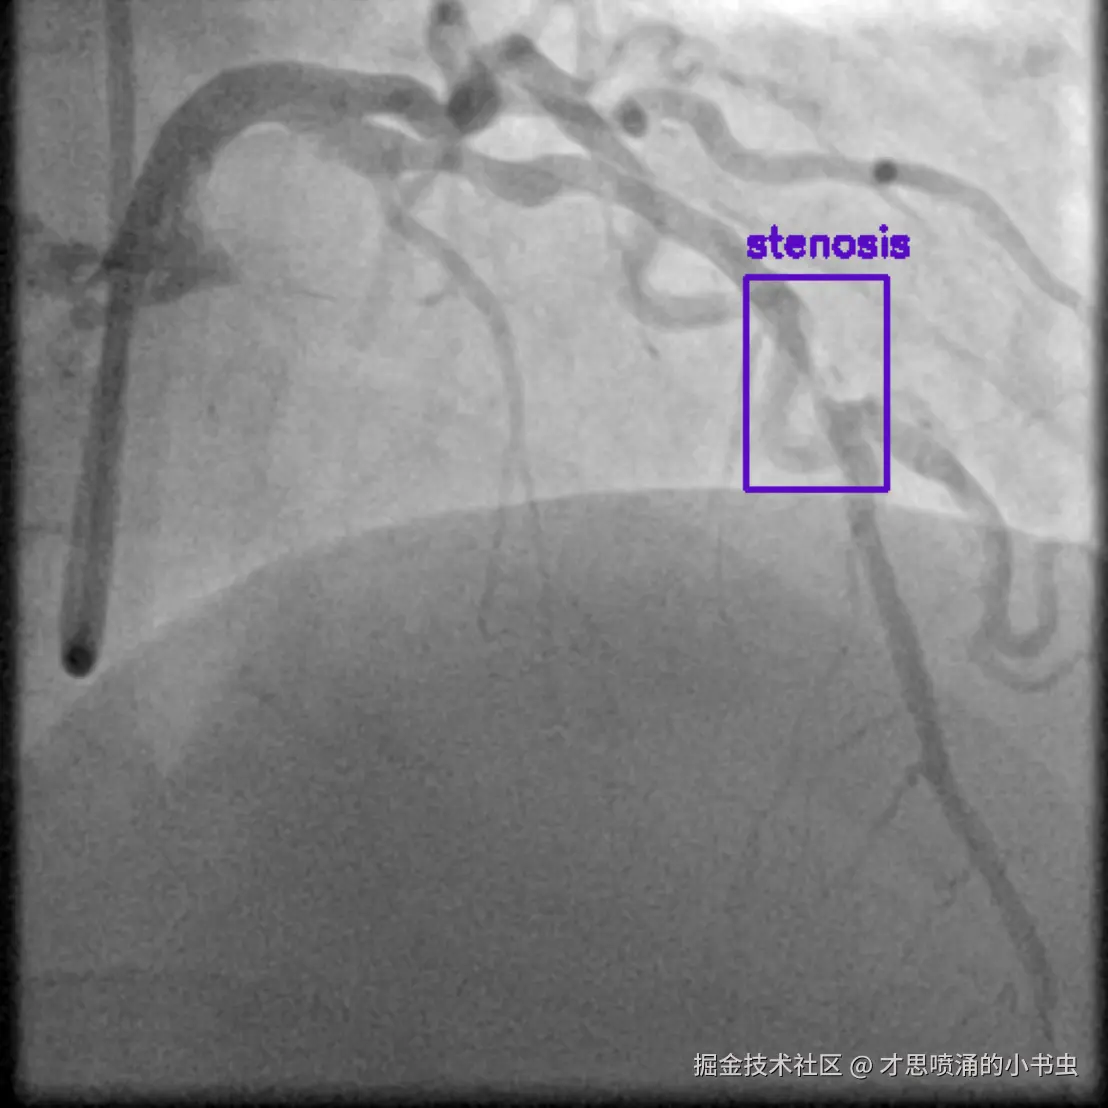

图1 X 射线冠状动脉造影图像,紫色高亮区域显示狭窄。狭窄表示血管变窄,限制了流向心肌的血流。